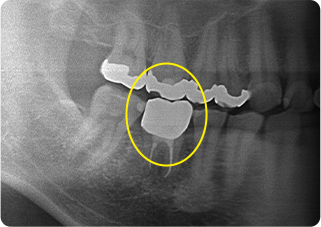

精密根管治療④

術前

術後

| 主訴 | 奥歯で噛むと痛い |

|---|---|

| 治療期間/回数 | 1ヵ月、3回 |

| 価格(税込) | 88,000円(税込) |

| リスク・副作用 | 病変再発、歯根破折の可能性 |

| ポイント | う蝕検知液を用い、むし歯の取り残しが無いようにし、ラバーダム防湿を行い、無菌的に根管治療を行った。根管充填材は、殺菌作用の強い保険適応外のMTAセメントを使用した。 |